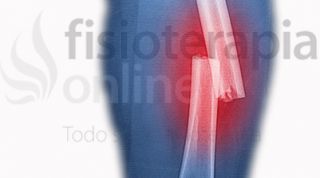

En general, la fractura se produce por la aplicación de una fuerza sobre el hueso, que supera su resistencia elástica, teniendo en cuenta que esta resistencia es una décima parte a la del acero.